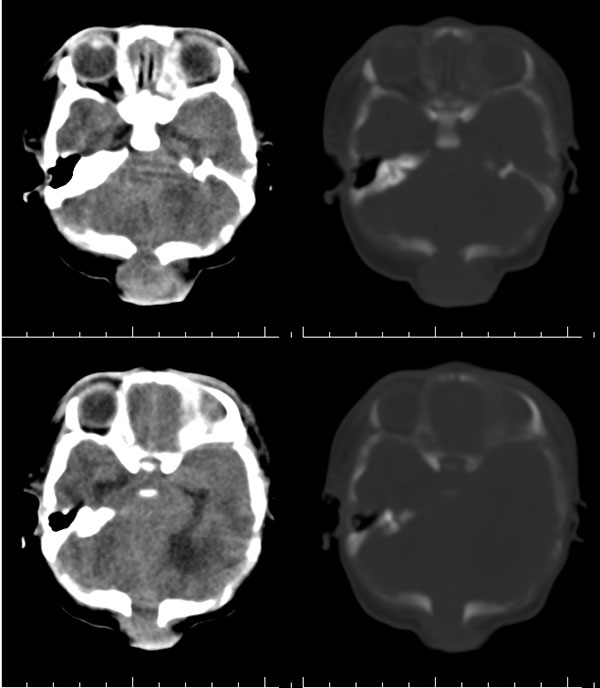

枕骨缺损,脑膜脑膨出。同时第4脑室挤压变形、闭塞,致使第3脑室、双侧侧脑室显著积水、扩张,过高的颅内压推挤脑实质,致使颅骨内板出现多而且深的脑回样压迹,脑细胞水肿,皮质、白质分界不清。

颅骨内面凹陷——过高的颅内压推挤脑实质,过高的颅内压推挤脑实质,致使颅骨内板出现多而且深的脑回样压迹

从图像分析看到的是三、侧脑室的积水,颅骨凹凸不平应是脑压高引起的,脑膜膨出是因脑压增大所致。综合考虑是:中脑水管发育畸形(狭窄或闭锁不全)并三、四脑室积水。枕骨发育不全伴脑脊膜膨出。